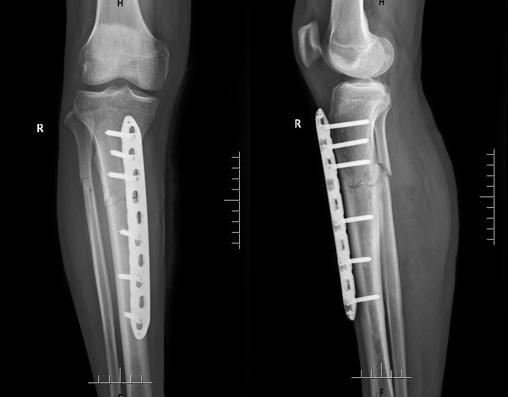

术前X线片检查

文章插图